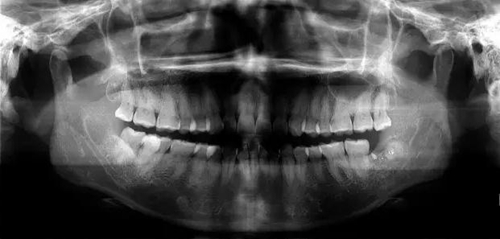

下面看一個病例,患者,女,30歲,因左下頜智齒嵌塞食物后疼痛,至當(dāng)?shù)匮揽平o予拔除,但術(shù)后1個半月,患者自覺拔牙區(qū)一直隱隱疼痛,時輕時重,遂來診。檢查發(fā)現(xiàn),拔牙創(chuàng)口一直未愈合,未見明顯腫脹,拍片發(fā)現(xiàn),拔牙窩內(nèi)顯示高密度斷根影

像,該斷根臨近下頜神經(jīng)管,同時發(fā)現(xiàn)第二磨牙遠中有兩塊高密度影像,疑似殘留骨片或牙片,應(yīng)該是引起疼痛的原因,經(jīng)與患者溝通,采納建議,進行二次拔牙。